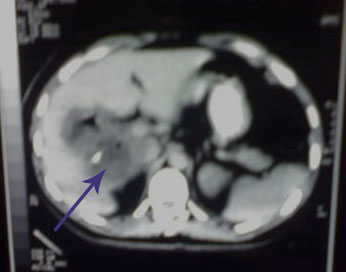

A 35 years old, male, developed fever and generalized bony aches, so he sought medical advise, received antibiotics and symptomatic treatment for one week but the condition sustained. So he was admitted to the fever hospital, diagnosed typhoid fever, received treatment, antipyretics for one week and discharged with little improvement. Days later the condition recurred with appearance of right hypochondrial discomfort . Our examination revealed high grade fever , toxic look, enlarged tender liver. CT: revealed a big hepatic abscess (arrowed).